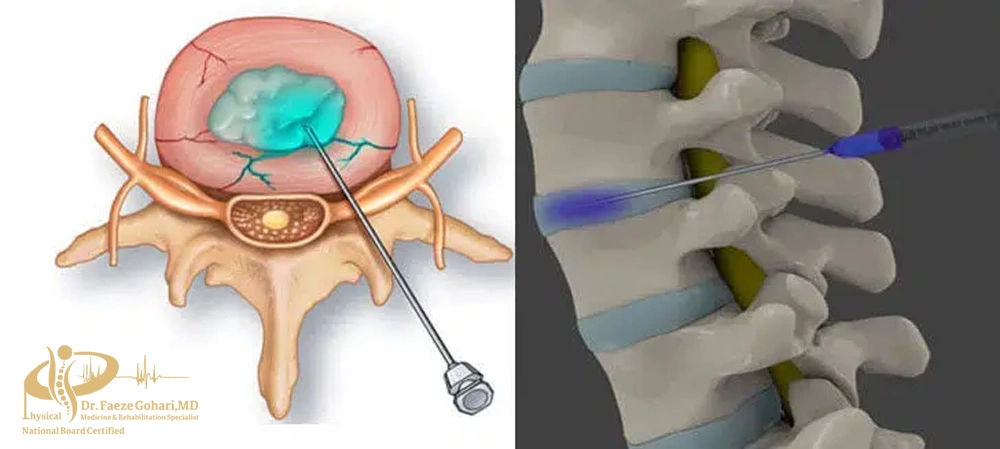

تزریق مستقیم به داخل دیسک (کوچککردن بیرونزدگی)

دیسککتومی، دقیقترین و مؤثرترین نوع اوزون تراپی برای دیسک کمر است. در این روش اوزون مستقیماً به داخل دیسک آسیبدیده تزریق میشود تا التهاب کاهش یافته و حجم بیرونزدگی کنترل شود. روندی که در بین عموم گاهی بهاشتباه «خشککردن دیسک» نامیده میشود.

این تزریق معمولاً برای افرادی انجام میشود که دچار فتق دیسک واقعی (بیرونزدگی دیسک) هستند و درد آن به پا تیر میکشد.

تزریق در نزدیکی دیسک (کاهش التهاب اطراف ریشههای عصبی)

در این روش، اوزون به ناحیهای نزدیک به دیسک و اطراف ریشههای عصبی تزریق میشود – نه به داخل خود دیسک. هدف از این تزریق، کاهش التهاب، کاهش فشار عصبی و تسکین دردهای تیر کشنده مانند سیاتیک است.

سوزن بادقت بالا در نزدیکی محل خروج عصب از ستون فقرات قرار میگیرد – در عمقی متفاوت از تزریقهای عضلانی.

این نوع تزریق معمولاً برای بیمارانی مناسب است که بیرونزدگی دیسک خفیفتری دارند یا درد آنها بیشتر ناشی از التهاب اطراف عصب است، نه فشار مستقیم از سوی دیسک.